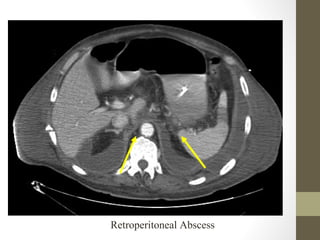

Retroperitoneal Abscess

Psoas Abscess

Radiology- CT Scan

• Detect leaking AAA (in stable patient)

• Evaluate for renal calculi, appendicitis, perforation (free air),

diverticulitis, abscess, mesenteric ischemia, masses, obstruction